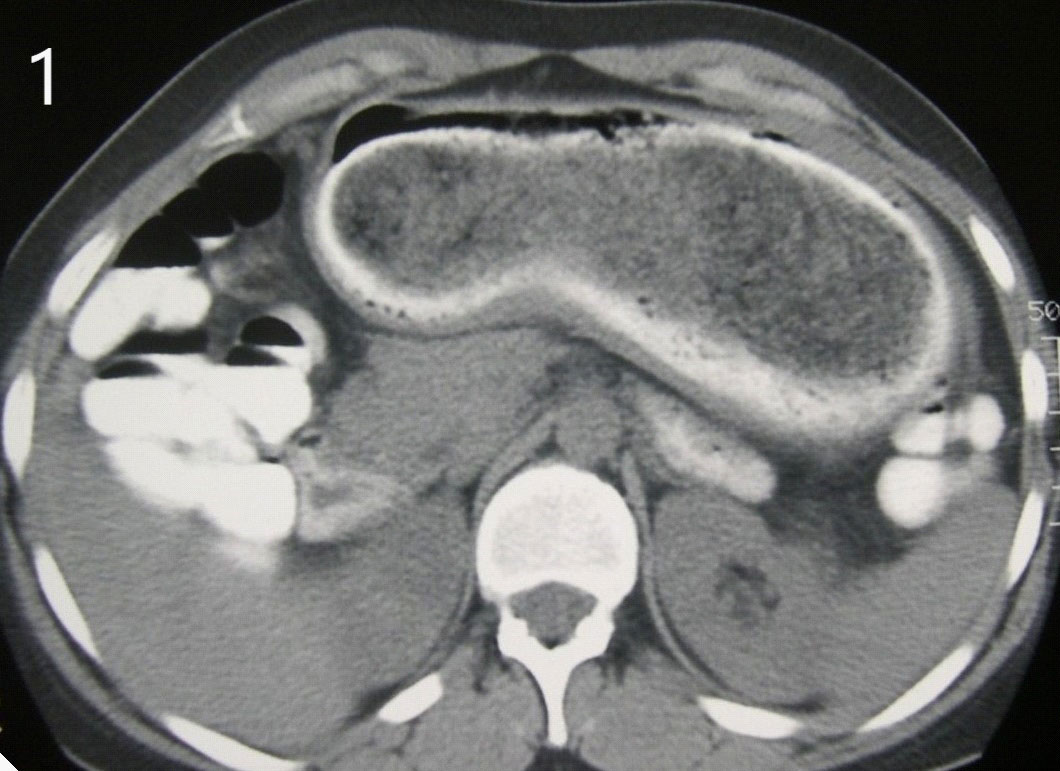

A 27-year-old woman presented to the emergency room with epigastric abdominal pain and intermittent vomiting of 4 days of evolution. The patient has a history of anxiety symptoms. Dehydration and a palpable hard-elastic mass in the epigastric region were observed during the physical examination. The laboratory analysis did not show significant alterations. In imaging studies, occupied gastric dilation with a heterogeneous formation was evidenced inside. Hospitalization (Figure 1) was decided, and an upper digestive video endoscopy was performed, through which an abundance of hairs was observed inside the stomach without the possibility of progression to the body and gastric antrum. Open surgery was decided, a median supraumbilical laparotomy was performed, a gastrostomy and a giant trichobezoar were extracted (Figures 2 & 3). The patient progressed favourably; She began with fluid intake at 24 hours and was discharged without complications at 72 hours. The patient was referred to control by surgery, gastroenterology and mental health departments.

Figure 1:Tomography: Gastric dilation with a heterogeneous formation inside.

In most cases, they are unique, and only 15% spread to the small intestine. The diagnosis is difficult because the patient usually denies or hides trichophagia or trichotillomania, which makes clinical suspicion difficult; Diagnostic methods include ultrasonography, contrast-enhanced CT, and gastrointestinal endoscopy. Abdominal ultrasonography can show an intragastric mass of high-amplitude echoes, with posterior acoustic shadowing, and barium-contrasted radiography shows us a typical "honeycomb" image, caused by part of the barium that is retained in the bezoar; however, CT is one of the more specific methods, showing a heterogeneous image that dilates the gastric cavity. Upper endoscopy is the test of choice, allowing us to observe the trichobezoar lodged in the gastric cavity directly and thus determine the therapeutic procedure [11,12].